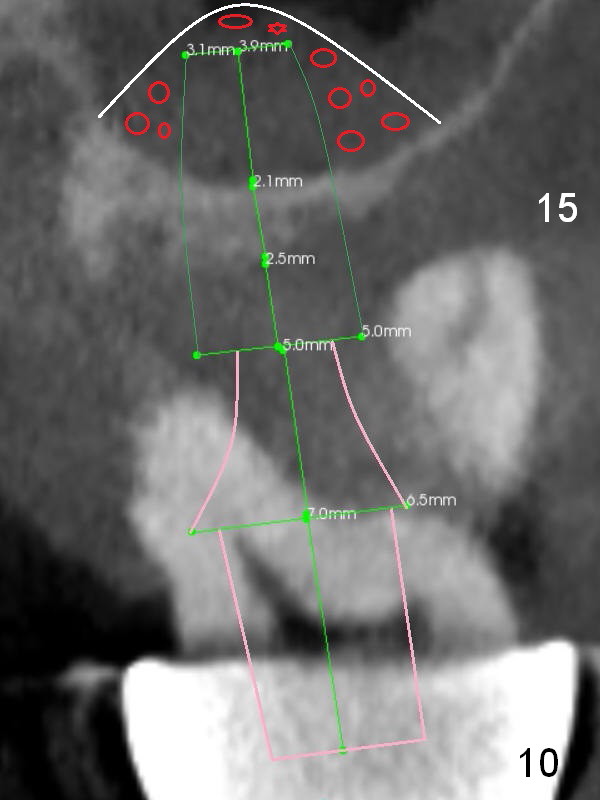

Alginate impression will most likely dislodge #11-15 loose FPD.  Start osteotomy at #11 and 15 first (Fig.6, 10) and use the teeth #9 and 10 as trajectory reference.  Prepare PRF (Fig.10 white curved line) and Magic Lifter for #15 (2 mm bone).  Red circles: bone graft.  Bone graft will be placed around the coronally exposed threads.